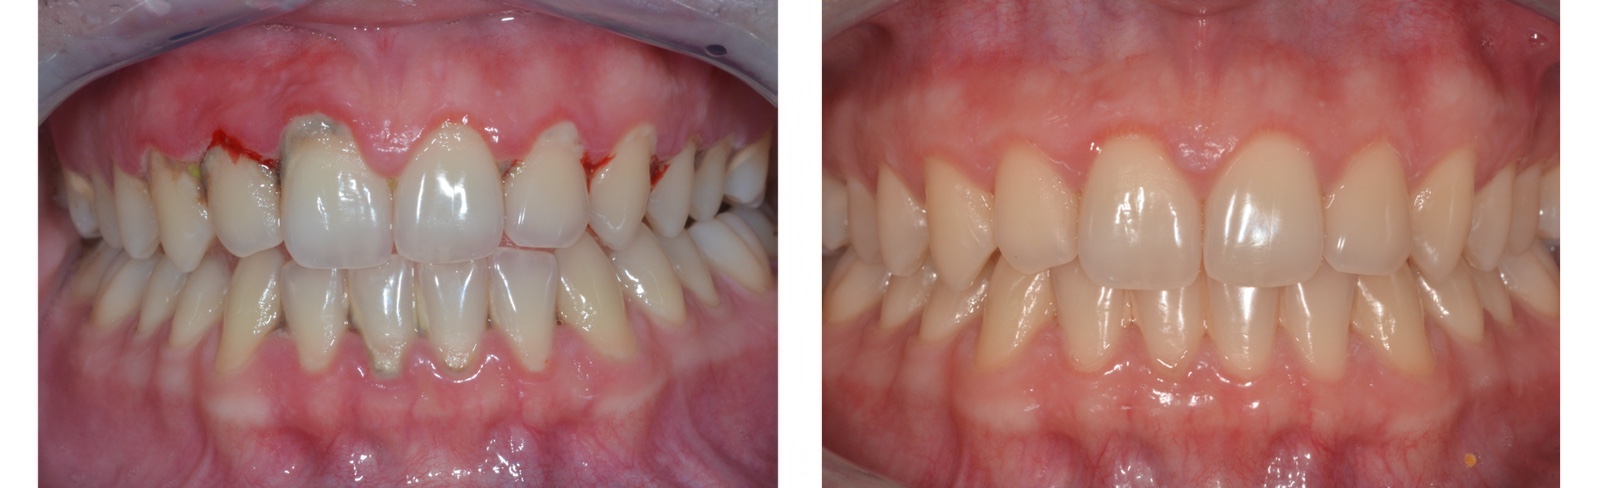

A rendszeres, íny és a csont állapotára is kiterjedő fogászati szűréssel meg lehet előzni a nagyobb bajt. Mégis sokan későn keresik fel a fogorvost, pedig ha idejében diagnosztizálásra kerül, számtalan lehetőség kínálkozik az instabillá vált fogak megmentésére.

Esetenként szükséges a fogak körüli csont, és ínytöbblet eltávolítása, úgynevezett koronahosszabbítás. Ez történhet esztétikai megfontolásból, illetve mély szuvasság esetén ha nincs elegendő foganyag egy tömés, korona vagy hídpótlás elkészítéséhez.